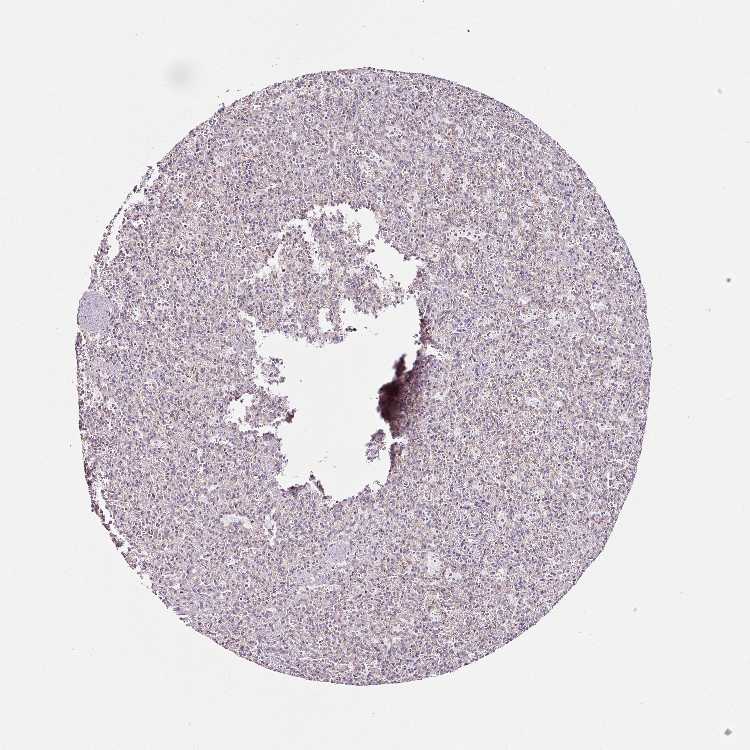

SPLEEN - Antibody stainingi

Antibody staining in the annotated cell types in the current human tissue is reported as not detected, low, medium, or high, based on conventional immunohistochemistry profiling in selected tissues. This score is based on the combination of the staining intensity and fraction of stained cells.

Each image is clickable and will lead to virtual microscopy that enables deeper exploration of all samples and also displays staining intensity scores, fraction scores and subcellular localization as well as patient and tissue information for each sample.

Antibody HPA041981Antibody CAB034929

Cells in red pulp LowNot detected

Cells in white pulp MediumNot detected